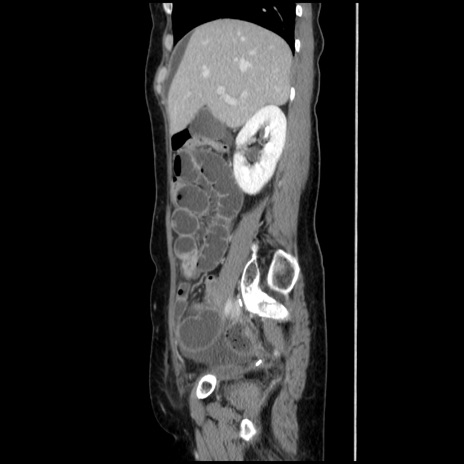

横断像

【症例】40歳代 女性

【主訴】上腹部痛、嘔気・嘔吐

【現病歴】約9時間前頃から急に上腹部痛、嘔気、嘔吐が出現。改善しないため救急要請。

【既往歴】子宮頚癌(広汎子宮全摘術、放射線療法)、腸閉塞

【身体所見】腹部:平坦、軟、腸雑音亢進、上腹部を中心に腹部全体に圧痛あり。

【データ】WBC 8400、CRP 0.03